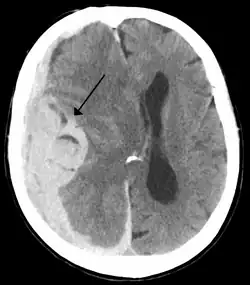

Midline shift is a shift of the brain past its center line.[1] The sign may be evident on neuroimaging such as CT scanning.[1] The sign is considered ominous because it is commonly associated with a distortion of the brain stem that can cause serious dysfunction evidenced by abnormal posturing and failure of the pupils to constrict in response to light.[1] Midline shift is often associated with high intracranial pressure (ICP), which can be deadly.[1] In fact, midline shift is a measure of ICP; presence of the former is an indication of the latter.[2] Presence of midline shift is an indication for neurosurgeons to take measures to monitor and control ICP.[1] Immediate surgery may be indicated when there is a midline shift of over 5 mm.[3][4] The sign can be caused by conditions including traumatic brain injury,[1] stroke, hematoma, or birth deformity that leads to a raised intracranial pressure.

Doctors detect midline shift using a variety of methods. The most prominent measurement is done by a computed tomography (CT) scan and the CT Gold Standard is the standardized operating procedure for detecting MLS.[5] Since the midline shift is often easily visible with a CT scan, the high precision of Magnetic Resonance Imaging (MRI) is not necessary, but can be used with equally adequate results.[5] Newer methods such as bedside sonography can be used with neurocritical patients who cannot undergo some scans due to their dependence on ventilators or other care apparatuses.[6] Sonography has proven satisfactory in the measurement of MLS, but is not expected to replace CT or MRI.[6] Automated measurement algorithms are used for exact recognition and precision in measurements from an initial CT scan.[7] A major benefit to using the automated recognition tools includes being able to measure even the most deformed brains because the method doesn’t depend on normal brain symmetry.[7] Also, it lessens the chance of human error by detecting MLS from an entire image set compared to selecting the single most important slice, which allows the computer to do the work that was once manually done.[7]

Midline shift measurements and imaging has multiple applications. The severity of brain damage is determined by the magnitude of the change in symmetry. Another use is secondary screening to determine deviations in brain trauma at different times after a traumatic injury as well as initial shifts immediately after.[3] The severity of shift is directly proportional to the likeliness of surgery having to be performed. The degree of MLS can also be used to diagnose the pathology that caused it. The MLS measurement can be used to successfully distinguish between a variety of intracranial conditions including acute subdural hematoma,[5][7] malignant middle cerebral artery infarction,[3] epidural hematoma, subarachnoid hemorrhage, chronic subdural hematoma, infarction, intraventrical hemorrhage, a combination of these symptoms, or the absence of pertinent damage altogether.[7]